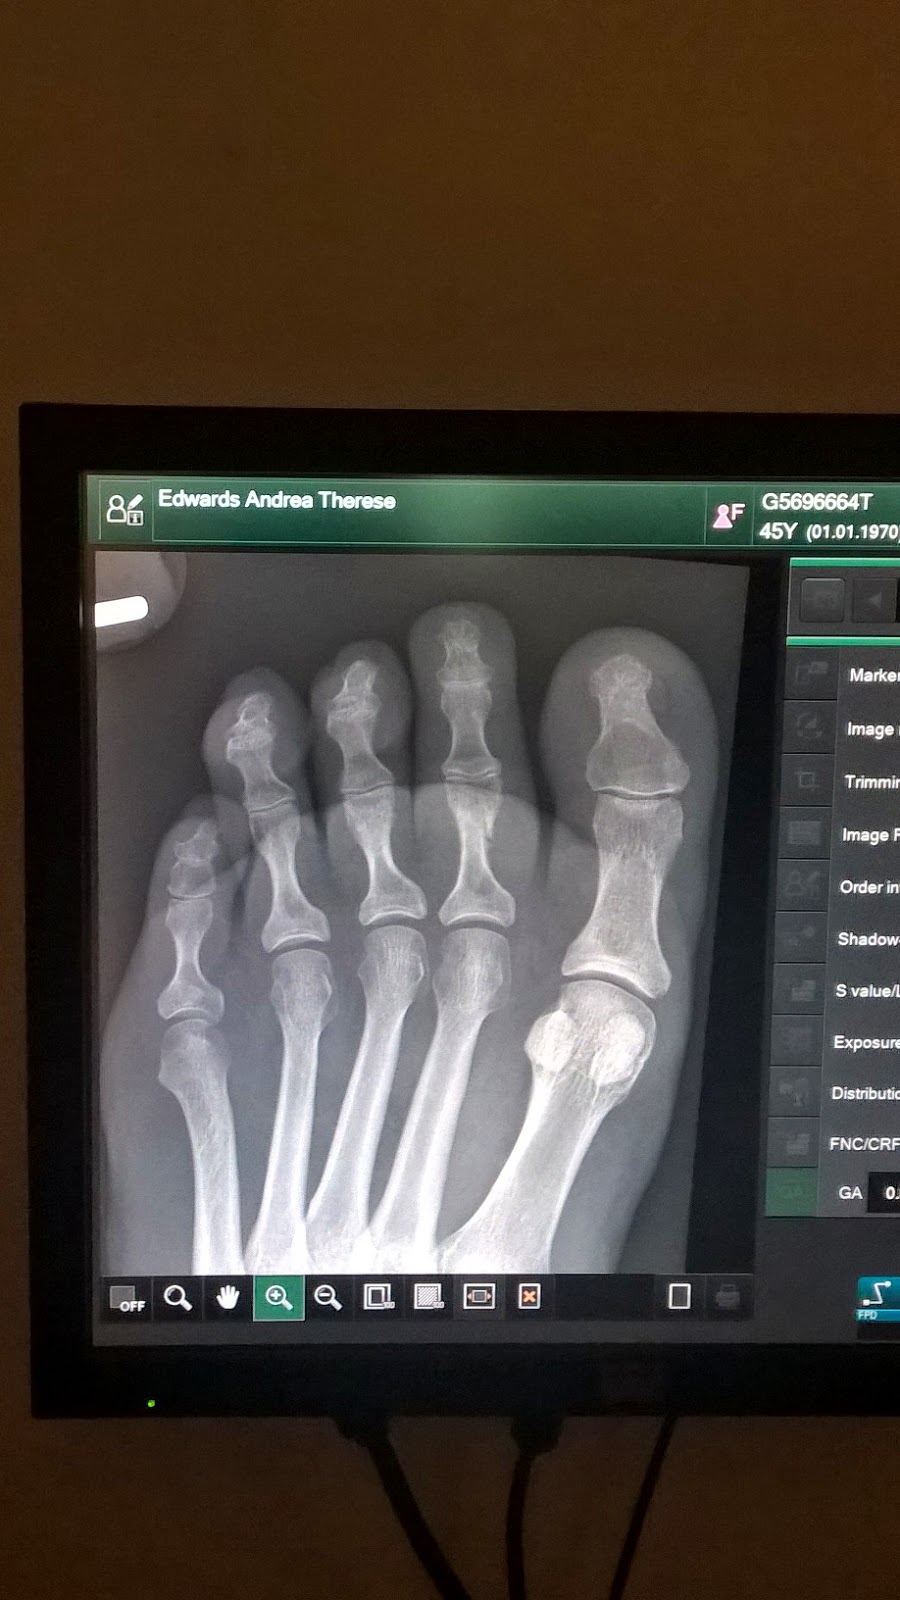

That was it – a fucked toe – SO annoying! It got fatter and fatter and fatter, and it wasn’t ‘til a month later I thought hey, maybe an x-ray would be a good idea? That’s when I got that little photo taken to discover I did, in fact, break it. On the mend now, but crikey, who knew how much a toe could hurt? The reason I didn’t do anything about my toe is what’s the point? Every time I’ve had anything foot related checked out by the doctor, they just tend to look at you with a little shrug and say keep it up and ice it, that’s all you can do – right?